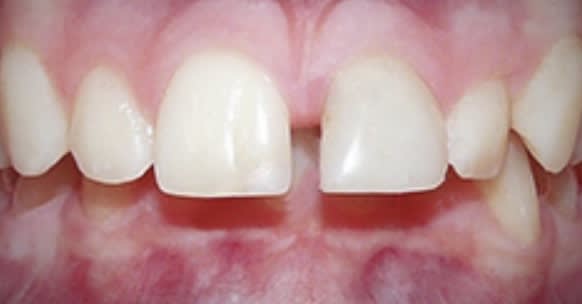

Sauf que si on fait un petit zoom , on s’aperçoit qu’il y a toujours un mini dédoublement. L’épaisseur de deux poils de cul. Sauf que si vous vous mettez deux poils de cul entre les dents , vous ne fermez pas à fond .....

--

524a9bb9 337c 400b 86d2 8c3015d6a6d8 unx1jf - Eugenol

Sinon pour un bon overbite , je veux enregistrer juste le secteur antérieur , les caméras font comment pour enregistrer l’occlusion et pour voir où sont les dents mandibulaires ? Comment peuvent elles placer correctement les deux arcades puisque les dents mandibulaires sont complètement recouvertes par les dents maxillaires ?